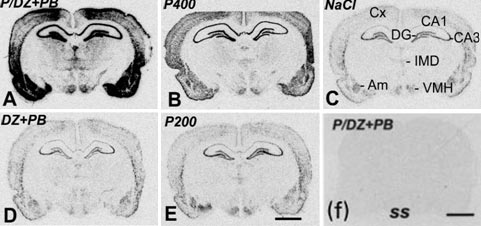

Super-induction of BDNF expression by anti-epileptic drugs in rat brain